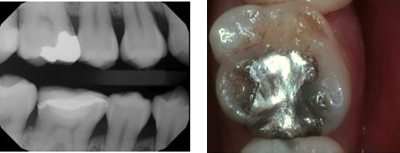

Before CEREC treatment

Before CEREC treatment

At Tao Dental Care, our cutting-edge digital technology allows us to

create the perfect precision restoration that will blend in

seamlessly with your natural teeth. We use beautiful tooth-colored

porcelain to precisely match the exact shade and translucency of

your teeth. Our restorative materials are strong and durable for a

smile that withstands the test of time.